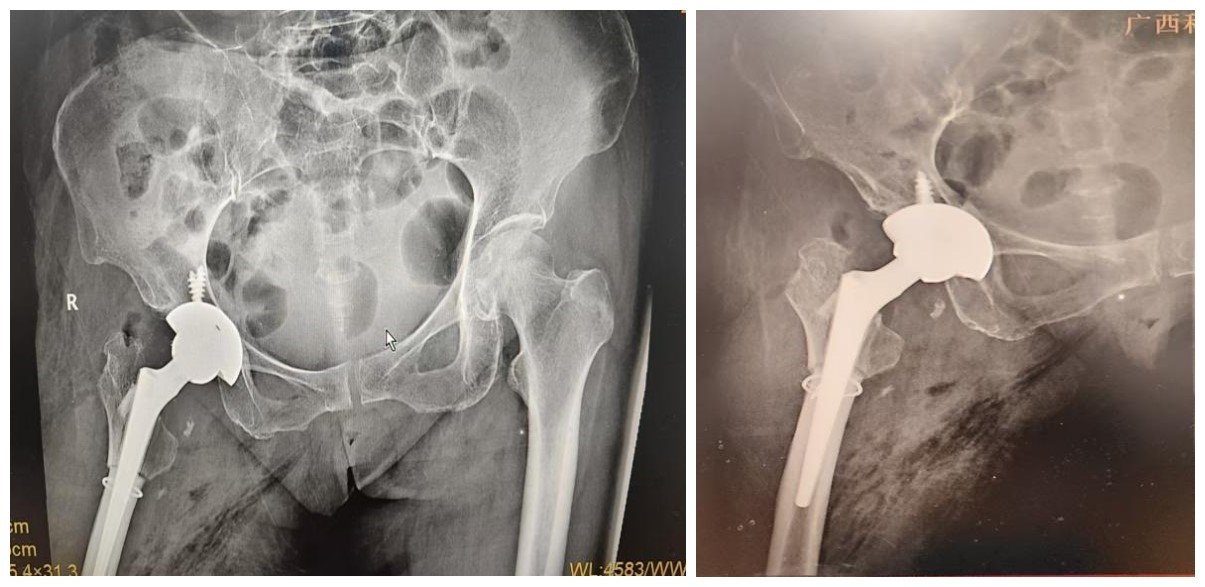

关节运动医学科团队全面评估病情、周密制定手术方案,与家属充分沟通,在排除手术禁忌证后,顺利为范阿姨实施右侧全髋关节置换+股骨转子下截骨术手术,精准顺利,一次性完成关节重建+畸形矫正+肢体等长三大目标。

术后效果:双下肢等长,疼痛显著缓解

术后复查结果喜人:双下肢基本等长,右髋疼痛明显减轻髋关节功能显著改善已顺利进入康复阶段,困扰60年的病痛,一朝解除。发育性髋关节发育不良(DDH)全髋置换术后第三天,在医护团队的指导与协助下,患者成功坐起床边。看到到患者状态渐好,家属脸上也露出了安心的笑容。每一个微小的进步,都是康复路上最好的鼓励。

术后